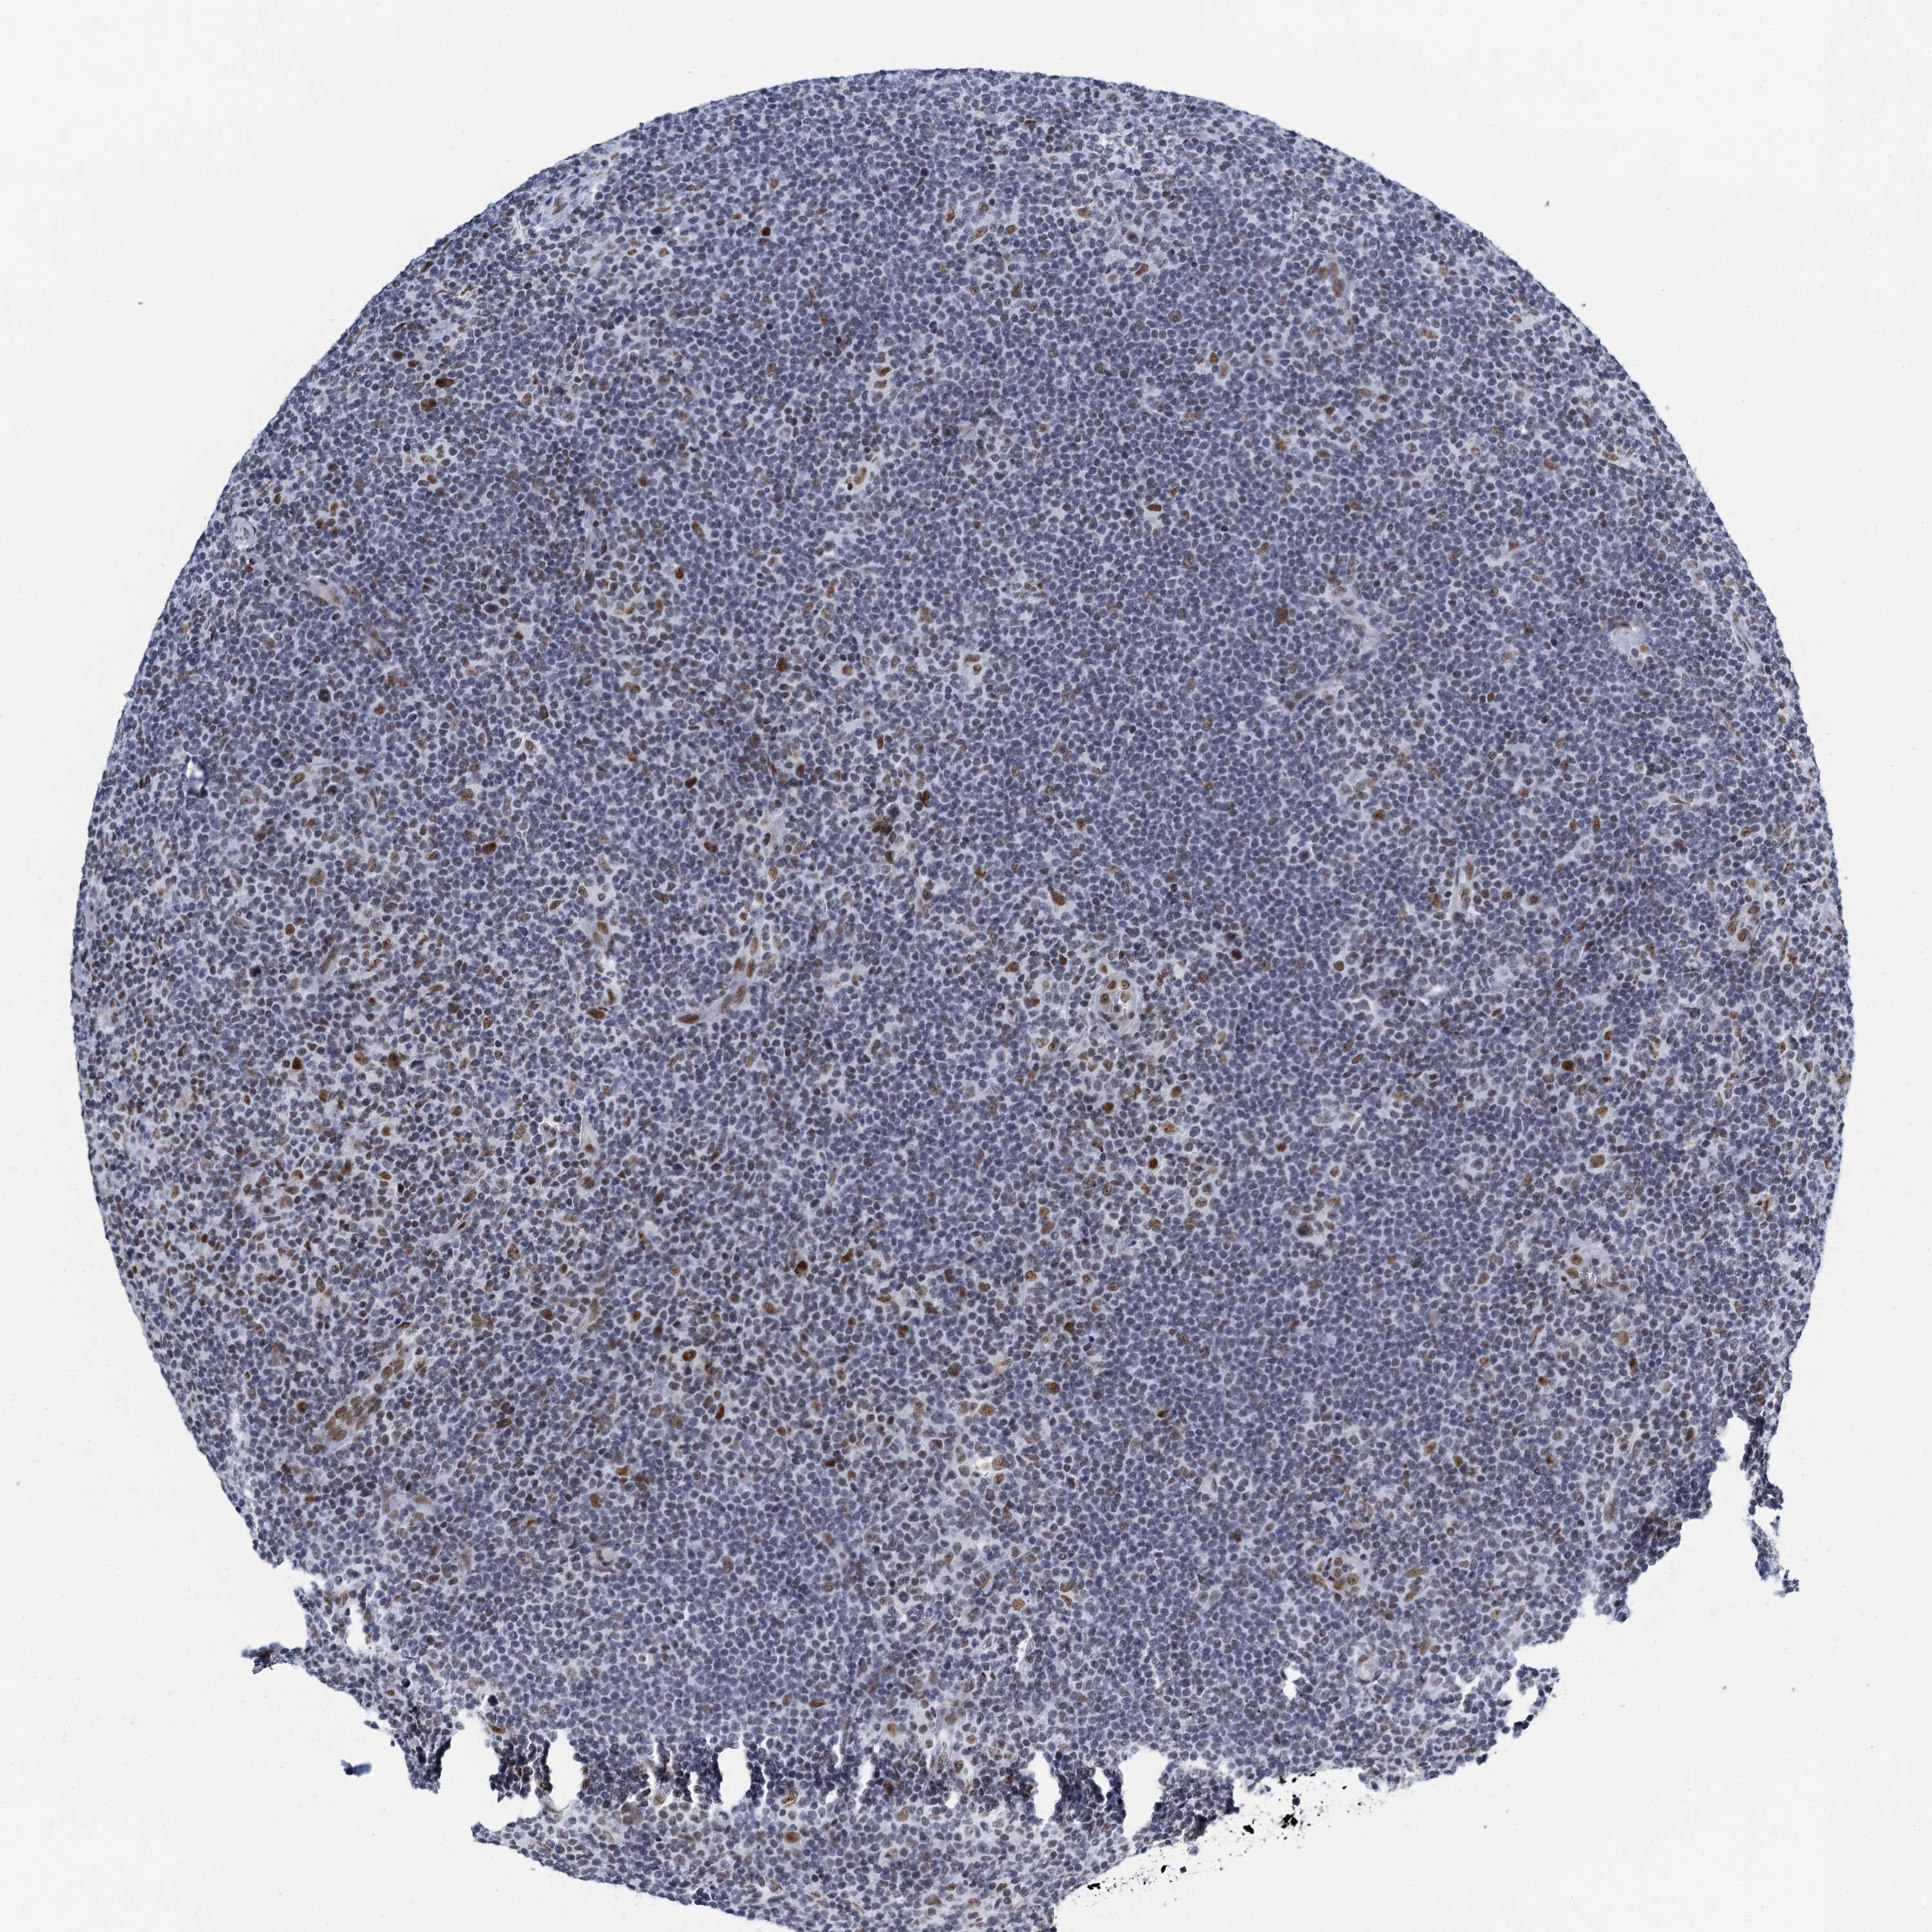

LYMPHOMA - Protein expressioni

A mouse-over function shows sample information and annotation data. Click on an image to view it in a full screen mode. Samples can be filtered based on level of antibody staining by selecting one or several of the following categories: high, medium, low and not detected. The assay and annotation is described here.

Antibody stainingi

Antibody staining in the annotated cell types in the current human tissue is reported as not detected, low, medium, or high, based on conventional immunohistochemistry profiling in selected tissues. This score is based on the combination of the staining intensity and fraction of stained cells.

Each image is clickable and will lead to virtual microscopy that enables deeper exploration of all samples and also displays staining intensity scores, fraction scores and subcellular localization as well as patient and tissue information for each sample.

Antibody HPA041632

Hodgkin's disease, NOS

Malignant lymphoma, non-Hodgkin's type, High grade

Malignant lymphoma, non-Hodgkin's type, Low grade